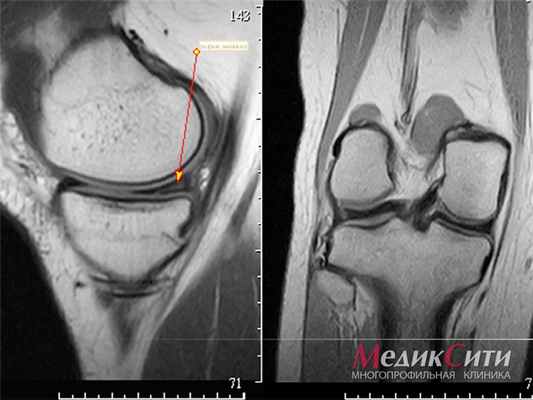

(Слева) Рентгенография в боковой проекции: на ладонной поверхности средней фаланги определяется овальное мягкотканное образование без каких-либо специфических признаков.

(Справа) У этого же пациента при рентгенографии в косой проекции помимо образования, визуализируются выраженные эрозивные изменения прилежащей кости, что является не типичным для фибромы сухожильного влагалища. Утолщение кортикального слоя в области эрозивных изменений указывает на медленный рост образования. (Слева) При МРТ в коронарной плоскости на Т1 ВИ (слева) и сагиттальной плоскости на Т2 ВИ в режиме FS (справа) выявленное образование характеризуется соответственно гипоинтенсивным и негомогенно гиперинтенсивным сигналом. В сагиттальной плоскости видно, что образование прилежит к сухожилию сгибателя. На обоих изображениях хорошо заметны эрозивные изменения кости.

(Справа) У этого же пациента при МРТ с контрастным усилением в аксиальной плоскости на Т1 ВИ в режиме FS выявленное образование характеризуется умеренным контрастированием и слабо гетерогенной структурой, что является типичным для фибромы сухожильного влагалища. Методами лучевой диагностики отличить ее от гигантоклеточной опухоли сухожильного влагалища не представляется возможным. (Слева) При МРТ в сагиттальной плоскости на Т1 ВИ наладонной поверхности запястья определяется овальное образование без каких-либо специфических признаков. Образование характеризуется гомогенно изоинтенсивным по сравнению с мышцами сигналом.

(Справа) При МРТ в сагиттальной плоскости на Т2 ВИ в режиме FS овальное образование с дольчатым контуром характеризуется относительно гомогенным гиперинтенсивным сигналом. Имеется лишь слабый намек на то, что образование содержит волнистые коллагеновые волокна. Без контрастного усиления такое образование сложно отличить от ганглиозной кисты, однако в этом случае была подтверждена солидная его структура (не показано).